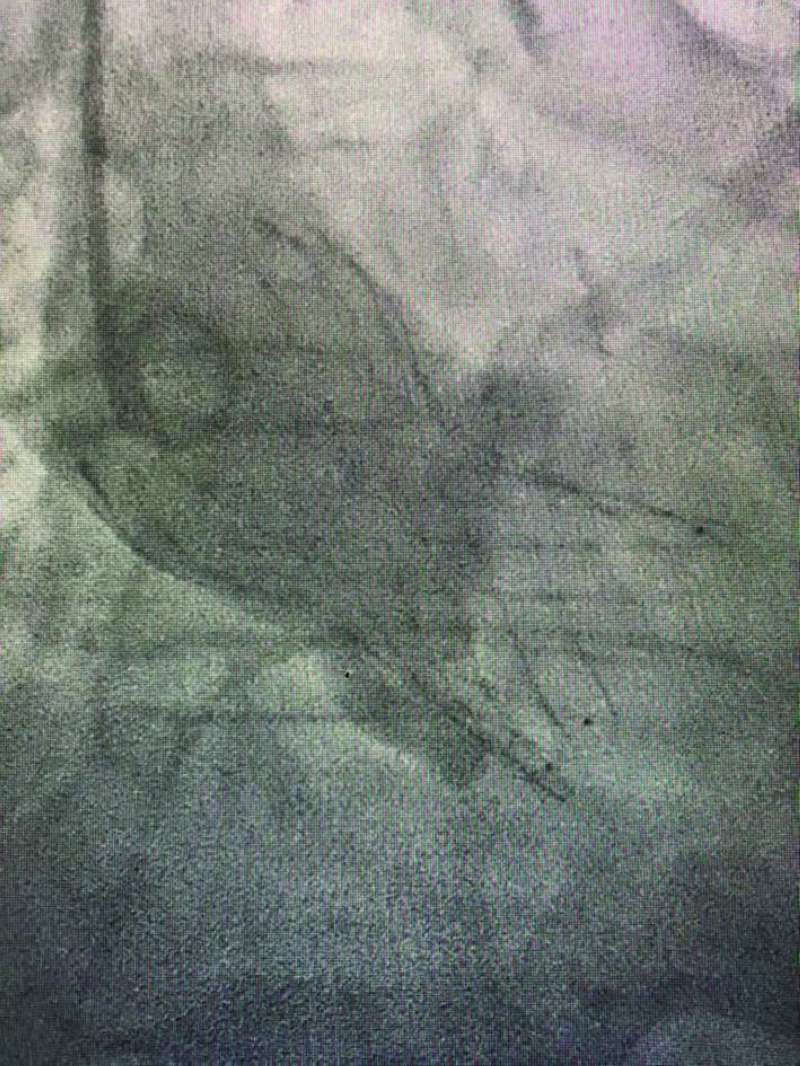

فقد استطاع الفريق تبديل صمام أورطي عن طريق القسطره (TAVI) باستخدام الصمام الحديث (EvolutFX) لمريضة في العقد السابع من عمرها، بعد إصابتها بضيق شديد بالصمام، مما أدى إلى دخولها إلى المستشفى بارتشاح رئوي.

وقال الدكتور العسعوسي لـ «الراي»، إن «المريضة كانت قد خضعت لعملية تبديل صمام ميترالي معدني في عملية قلب مفتوح منذ عشر سنوات، فيما كانت المسافة بين الصمام المعدني ومكان وضع الصمام الأورطي الجديد لا تتجاوز 2 مليمتر، وهى أقل مسافة ذُكرت في التقارير الطبية العالمية فى مثل هذه الحالات النادرة».

وأضاف «ساعدت التقنية الجديدة في الصمام، بوجود طبقة تساعد على ثباته بوضعه المحدد بدقة في هذه المسافة الضئيلة،على نجاح عمل تبديل الصمام. وقد تمت الاستعانه بسونار القلب عن طريق المريء وتقنية الإيكو ثلاثي الأبعاد (3D TOE) لتثبيت ووضع الصمام بدقة شديدة من دون التداخل مع شرفات الصمام الميترالي المعدني. وتعد هذه الحالة الأولى من نوعها في الشرق الأوسط، من الحالات النادرة عالمياً، التي يتم فيها تبديل الصمام الأورطي عن طريق القسطرة بوجود صمام ميترالي معدني باستخدام مثل هذه التقنيات الحديثة».